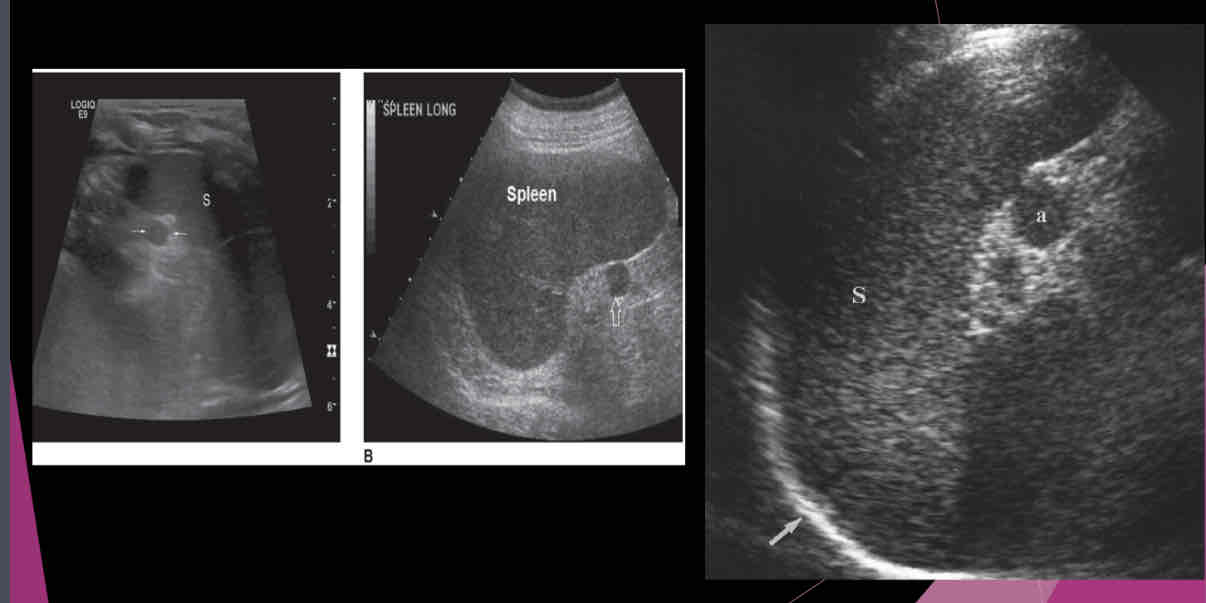

Describe the spleen on US?

-Homogeneous texture

- Echogenicity the same as or slightly below the normal liver echogenicity

- Smooth border at diaphragm

- Intercostal coronal view used to obtain spleen length

- Average length 11-13cm; usually decreases in size with age

- Usually 2/3 size of the liver

- Deep inspiration usually necessary to evaluate the entire organ

What is a relatively common anatomic variant?

accessory spleen (Splenule)

Most accessory spleens are small and measure between…

1.5 and 2.0 cm

An accessory spleen or splenule is _______ to spleen

hypoechoic

Isoechoic

hyperechoic

heterogeneous

Isoechoic